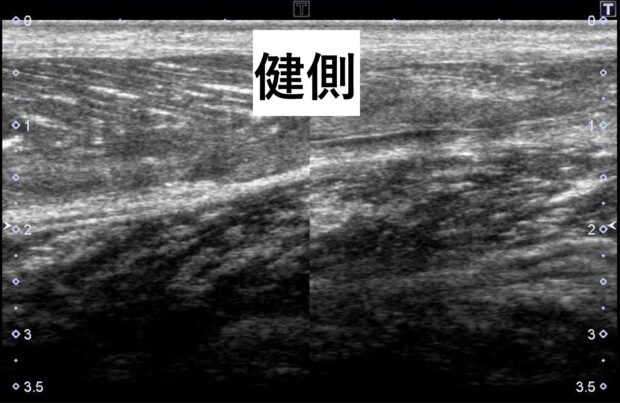

下記のエコー画像が打撲をした時の血腫(黒い部分)です。

血腫を放置すると骨化性筋炎に移行する可能性が高くなります!!